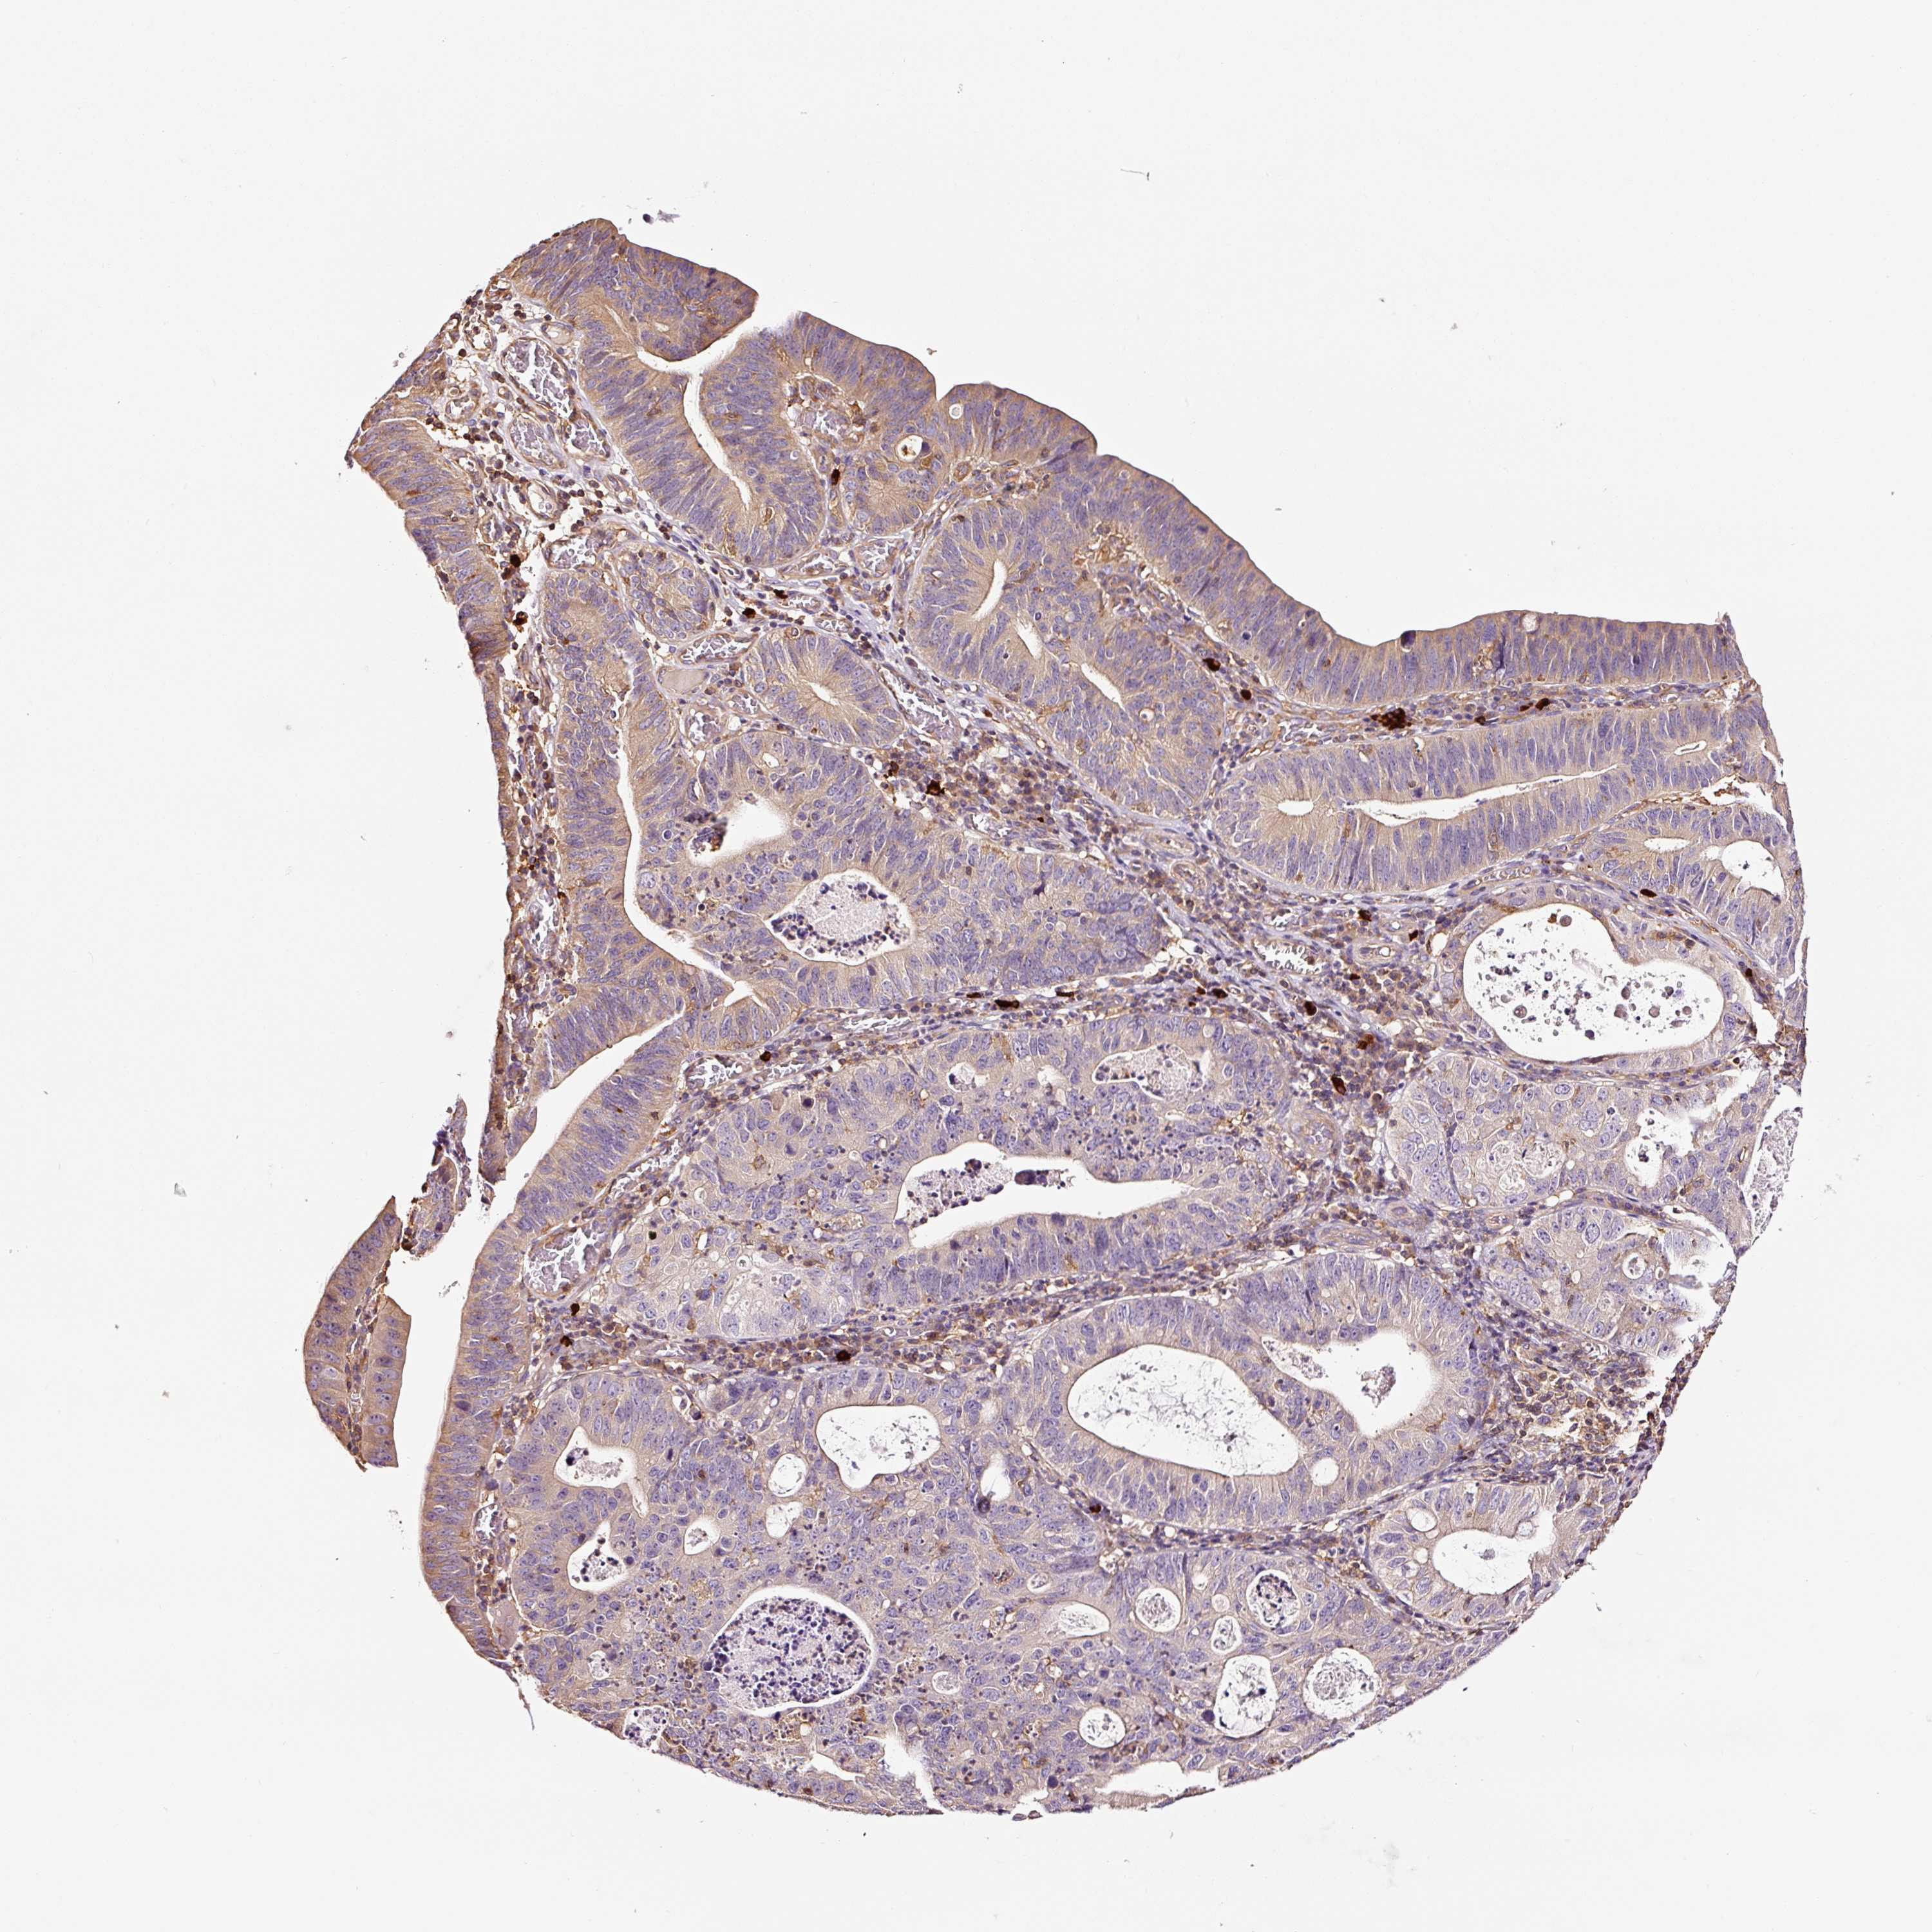

STOMACH CANCER - Protein expressioni

A mouse-over function shows sample information and annotation data. Click on an image to view it in a full screen mode. Samples can be filtered based on level of antibody staining by selecting one or several of the following categories: high, medium, low and not detected. The assay and annotation is described here.

Note that samples used for immunohistochemistry by the Human Protein Atlas do not correspond to samples in the TCGA dataset.

Antibody stainingi

Antibody staining in the annotated cell types in the current human tissue is reported as not detected, low, medium, or high, based on conventional immunohistochemistry profiling in selected tissues. This score is based on the combination of the staining intensity and fraction of stained cells.

Each image is clickable and will lead to virtual microscopy that enables deeper exploration of all samples and also displays staining intensity scores, fraction scores and subcellular localization as well as patient and tissue information for each sample.

Antibody HPA037997

Antibody HPA037998

Antibody CAB025485

Staining

Adenocarcinoma, NOS